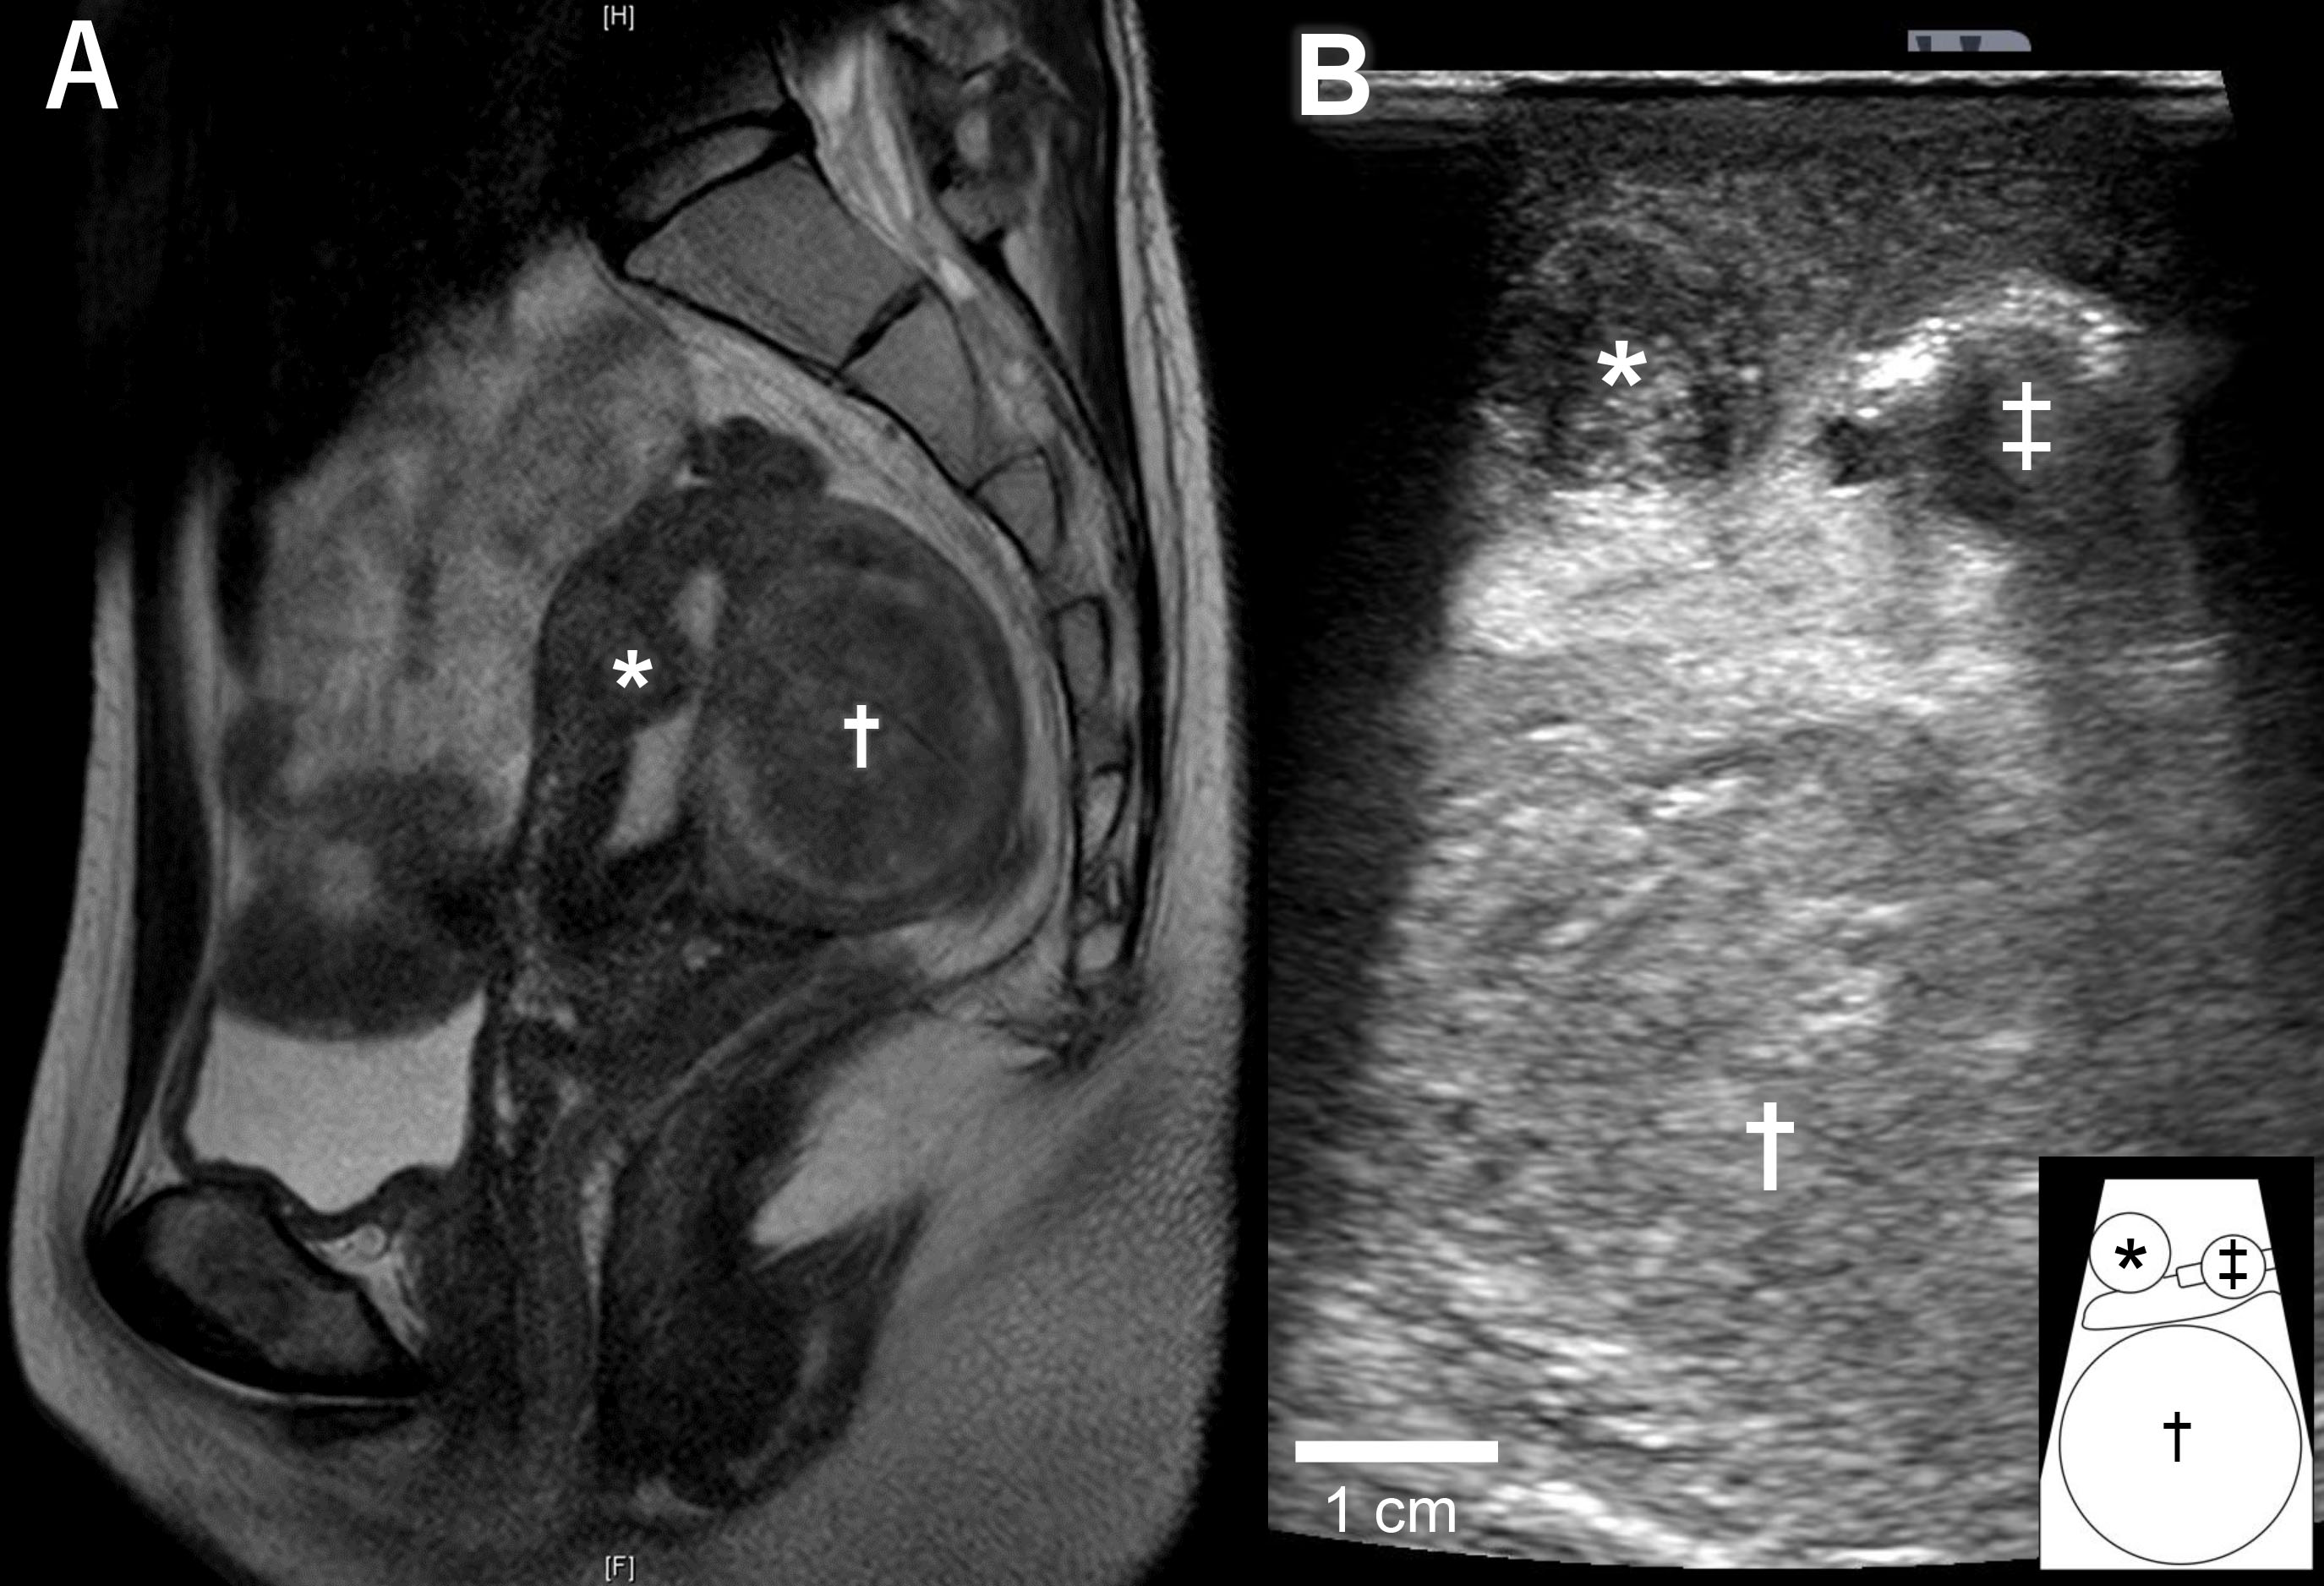

A 36-year-old nulligravida woman visited our clinic for an evaluation of her infertility. She was healthy, and her menses were regular and normal. Transvaginal ultrasonography revealed a type 2 submucosal myoma with a 60% myometrial extension measuring 15 mm in the anterior uterine wall and a type 4 intramural myoma (classified via guidelines from the International Federation of Gynecology and Obstetrics) measuring 49 mm in the posterior uterine wall. Magnetic resonance imaging suggested that the posterior myoma was a cellular leiomyoma (Fig. 1A). To make a definitive diagnosis regarding the intramural myoma, we planned a laparoscopic myomectomy. Furthermore, we planned to laparoscopically resect the submucosal myoma considering the myoma’s negative effect on implantation. Since the submucosal myoma was not visible from the external side of the uterus, we planned to use LUS to detect it. The location of the submucosal myoma was preoperatively assessed by transvaginal ultrasound sonography and magnetic resonance imaging. We measured the depth from the external side and the distance from the midline and fundus of the uterus. During the surgery, we used an ultrasound machine (Aplio a verifia CUS-AA000, Canon Medical Systems, Otawara, Tochigi, Japan) and a transducer (Linear array transducer PET-805LA, Canon Medical Systems, Otawara, Tochigi, Japan) with the detection frequency set at 7.0 MHz. We inserted the transducer through a 12-mm trocar (Fig. 1B). The submucosal myoma was visualized successfully with LUS immediately after the transducer was placed on the anticipated area of the anterior wall. Vasopressin (2 units diluted in 10 mL of saline) was injected precisely between the myoma and the myometrium under ultrasonography guidance (Fig. 2A,B). LUS also confirmed that the injected vasopressin effectively spread between the myoma and the myometrium (Fig. 2C). Using laparoscopic forceps and monopolar cautery, both the submucosal and the intramural myomas were successfully removed from the uterus without breaching the endometrium (Fig. 3A,B). The myomas were morcellated in a bag so that small fragments would not be scattered into the peritoneal cavity. The myoma beds were sutured to double to triple-layer closure with absorbable surgical thread. The postoperative course was uneventful, and the patient was discharged from the hospital as scheduled. No abnormal signs were detected at hospital visits 1 and 3 months after the surgery, and the initiation of fertility treatment was planned for 6 months after the surgery.

Fig. 2.Injection of vasopressin during laparoscopic myomectomy. (A) Intraperitoneal image during laparoscopic surgery. Diluted vasopressin was injected under ultrasonography guidance. (B) Injection needle (white arrowhead) was inserted to the boundary between the myoma and the myometrium. (C) Injected vasopressin spread in the layer between the myoma and the myometrium.